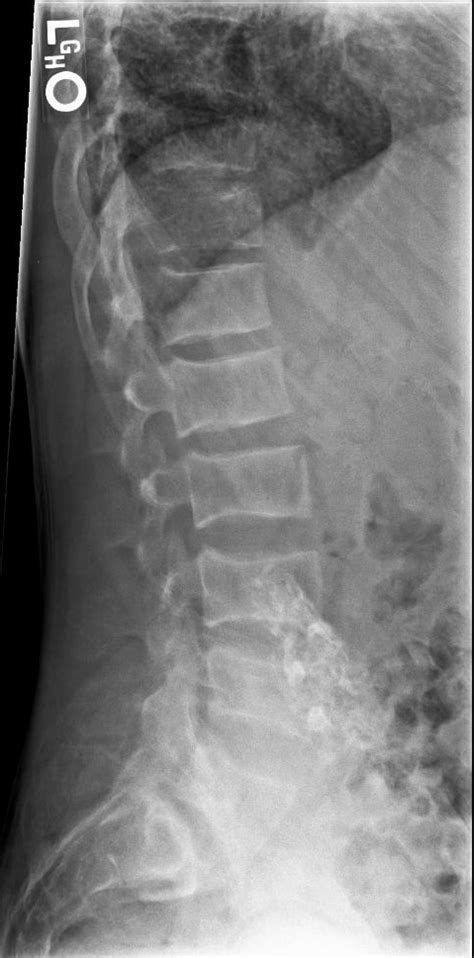

Now, where does a bone scan fit into all this? A bone scan, also known as a bone scintigraphy, is a powerful imaging technique that helps doctors visualize areas of abnormal bone activity. It involves injecting a small amount of radioactive tracer into your bloodstream. This tracer travels throughout your body and collects in areas where there’s increased bone metabolism or repair. Think of it like a highlighter for your bones, pointing out where the action is happening. For renal osteodystrophy, a bone scan can reveal areas of increased bone turnover , which often occurs as the body tries to compensate for the mineral imbalances. It can also help identify fractures that might not be easily visible on regular X-rays, especially stress fractures or subtle breaks. The scan provides a whole-body view , which is super beneficial because bone problems related to kidney disease can affect multiple areas. Doctors can use the information from a bone scan to help diagnose renal osteodystrophy, assess its severity, and monitor how treatment is working. It’s not just about seeing the damage; it’s about understanding the process that’s happening within the bones. The sensitivity of bone scans allows for the detection of metabolic bone disease before significant structural changes are apparent on plain radiography. This early detection is crucial for initiating timely interventions that can help preserve bone integrity and reduce the risk of debilitating fractures. The distribution and intensity of tracer uptake can offer clues about the specific type of bone disease present, guiding further diagnostic and therapeutic decisions. For instance, a generalized increase in uptake might suggest a widespread metabolic issue, while focal uptake could indicate a fracture or a more localized bone lesion. The dynamic nature of bone remodeling in renal osteodystrophy means that scans can be particularly informative, capturing the body’s ongoing attempts to repair and remodel compromised bone tissue. Therefore, the bone scan is not merely a static image but a functional assessment of bone health in the context of kidney disease. The detailed information it provides is invaluable for clinicians managing patients with CKD, helping them to navigate the complexities of bone health and make informed decisions about patient care. It’s a truly remarkable tool in the diagnostic arsenal for this condition.

When it comes to renal osteodystrophy , a bone scan is incredibly valuable because it can detect subtle changes that might be missed by other imaging methods. It’s particularly good at highlighting increased bone turnover , which is a hallmark of this condition. This increased turnover is the body’s way of trying to repair or remodel weakened bones that are struggling due to the imbalances in calcium, phosphorus, and vitamin D caused by kidney failure. The scan can pinpoint specific areas where this process is most active. Another crucial thing a bone scan can detect is fractures . In patients with renal osteodystrophy, bones become fragile and brittle, making them susceptible to fractures, even from minor stress or trauma. These fractures might be small or located in areas that are hard to see on standard X-rays. A bone scan will light up these fracture sites because the bone around a fracture is undergoing rapid repair and remodeling, attracting more of the radiotracer. Beyond just fractures and general turnover, the scan can also help identify bone pain origins. If you’re experiencing bone pain, the scan can show if it’s related to areas of increased bone activity, helping doctors understand the cause of your discomfort. It can even help differentiate between different types of bone abnormalities associated with kidney disease, such as osteomalacia or osteitis fibrosa cystica, by the pattern of tracer uptake. While it doesn’t provide the detailed soft tissue or internal bone structure information that an MRI or CT scan does, its strength lies in its sensitivity to metabolic changes and its ability to visualize the entire skeleton. This makes it an indispensable tool for assessing the systemic impact of renal osteodystrophy on bone health. The sensitivity of bone scintigraphy in detecting increased osteoblastic activity means it can often identify abnormalities at an earlier stage than conventional radiography, allowing for earlier intervention and potentially mitigating the progression of bone disease. This early detection is crucial for preventing severe complications like debilitating fractures and chronic pain, thereby improving the overall quality of life for individuals living with kidney disease. The comprehensive skeletal survey provided by a bone scan is essential for understanding the full extent of skeletal involvement, aiding in the development of personalized treatment plans. It’s truly a window into the dynamic state of your bones.